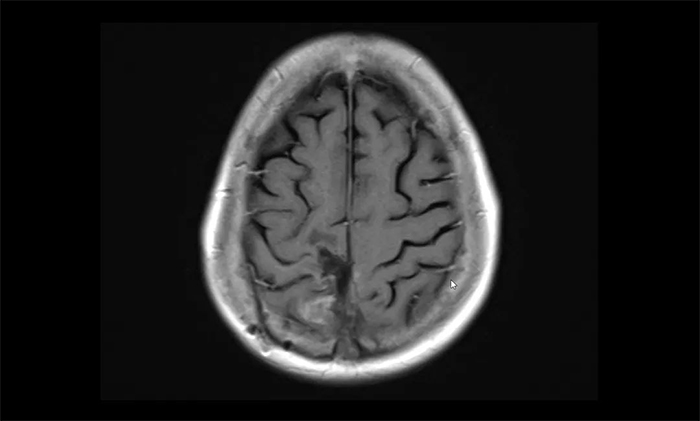

▲ 治疗后检查显示,病灶明显缩小

近期患者复查,肿瘤病灶较治疗前明显缩小,周围水肿明显减轻。患者原本偏瘫的左侧肢体恢复了活动能力,摆脱了轮椅,可自行走动,日常生活基本可自理。